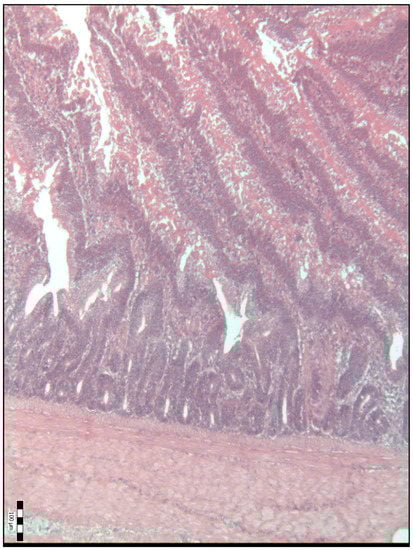

| Duodenal villi height (μm) | 718.50 a (584.50–841.50) | 834.00 b (695.00–990.00) | 992.00 c (814.50–1111.50) | 886.00 bcd (697.00–1134.50) | 798.50 bde (658.75–1088.00) | <0.001 |

| Base width of the duodenal villi (μm) | 48.00 a (38.00–68.00) | 59.00 b (52.00–69.50) | 67.00 bc (51.00–77.25) | 54.00 bd (45.50–67.00) | 65.00 ce (58.75–75.25) | <0.001 |

| Duodenal villi crypt depth (μm) | 78.00 a (66.00–93.00) | 85.00 a (75.50–93.50) | 71.50 b (63.75–80.25) | 64.00 c (54.00–74.50) | 78.00 ad (70.00–85.25) | <0.001 |

| The Villus Height-to-Crypt Depth Ratio | 8.86 a (7.16–10.60) | 9.81 b (8.51–12.09) | 14.24 c (11.64–16.36) | 13.61 cd (10.54–16.70) | 10.89 be (8.70–12.73) | <0.001 |